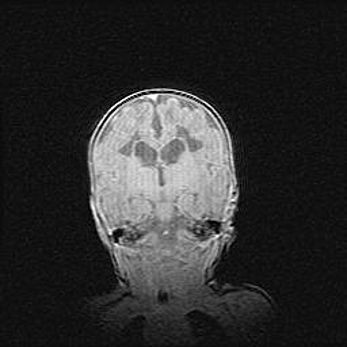

Сообщающаяся гидроцефалия. Кистозная энцефаломаляция головного мозга.

Возраст: 3 месяца 4 дня

Вес: 3100 г

Пол: женский

Окружность головы: 34 см

Срок гестации: 31 неделя

Кистозная энцефаломаляция головного мозга - одна из форм поражения головного мозга в детском возрасте. Характеризуется возникновением множественных и распространённых кист в коре, белом веществе и подкорковых образованиях головного мозга у плодов, новорождённых и детей раннего возраста. Развитие кистозной энцефаломаляции связано с внутриутробной асфиксией и гипотонией, родовой травмой, тромбозом синусов, пороками развития сосудов, инфекциями, сепсисом и другими причинами. Наиболее значимые инфекционные агенты: вирусы простого герпеса, цитомегалии, краснухи, токсоплазмы, энтеробактерии, золотистый стафилококк и другие.